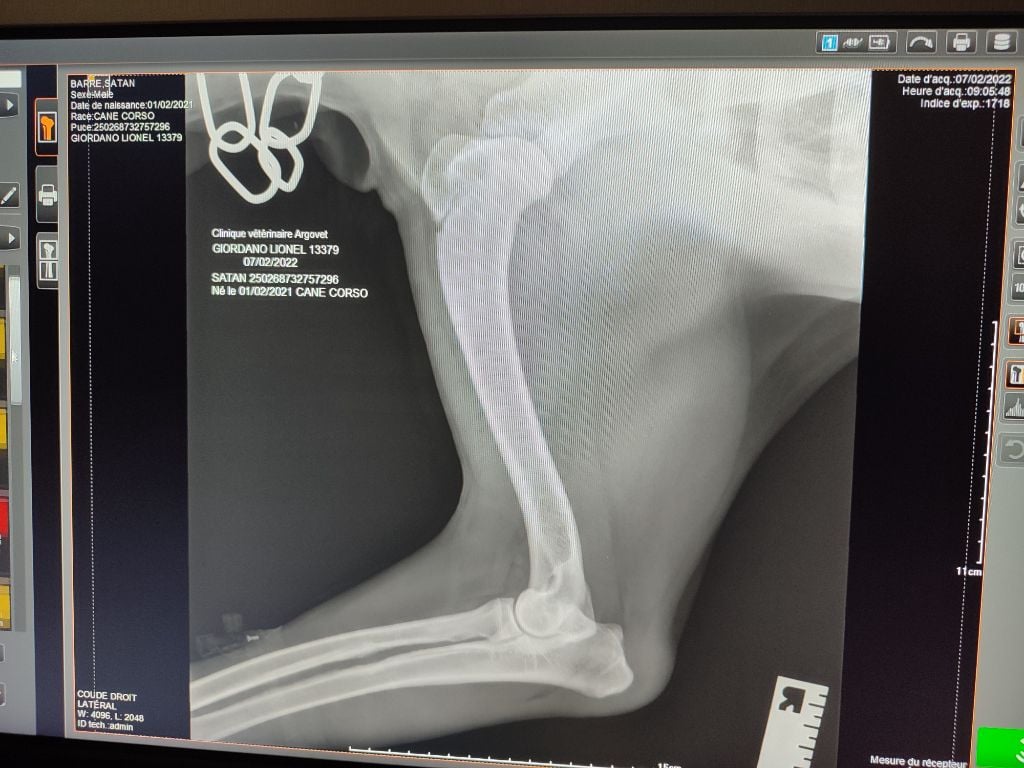

Radiographier hanches B et coudes 0

Radiographier hanches B et coudes 0